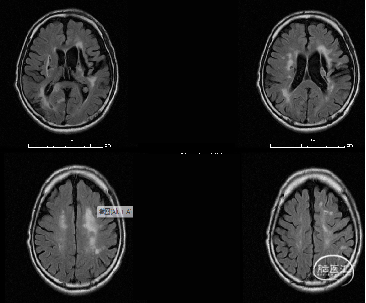

MR:双侧后循环散在急性梗死病灶(双侧小脑半球、双侧枕叶、胼胝体压部、右侧脑桥臂、桥脑右侧部及中脑被盖左侧)。MRA示:双侧椎动脉颅内段及基底动脉明显变窄。